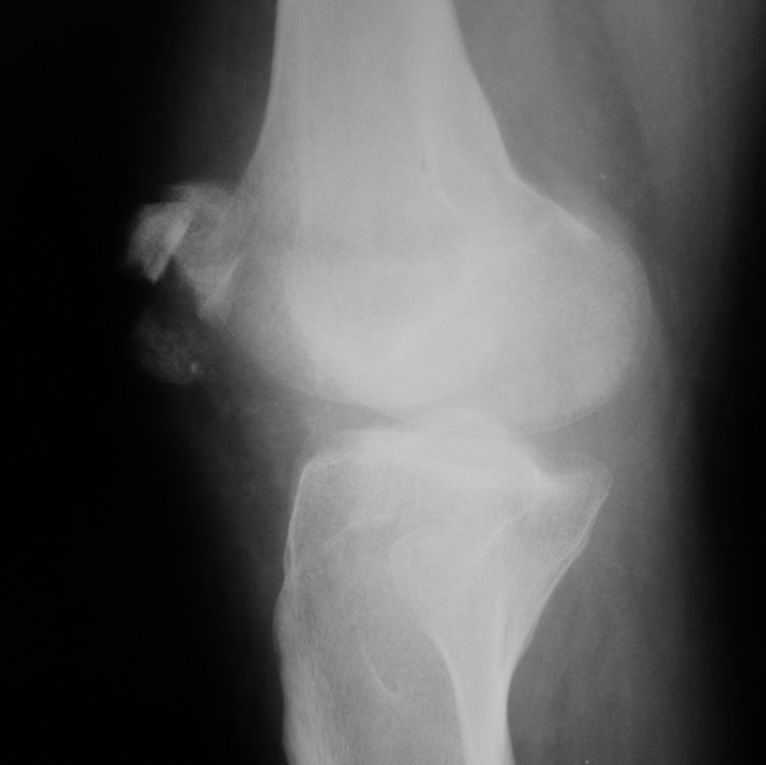

Уважаемые коллеги! Обратился пациент 32 лет с травмой коленного сустава от июля 2008 года - падение с мотоцикла, прямой удар передней поверхностью коленного сустава. Диагноз - открытый оскольчатый перелом надколенника. В одной из больниц города выполнили ПХО, шов надколенника лавсаном. Заживление раны с частичным нагноением(разведена на участке 3 см).

Сейчас мягкие ткани в порядке. R-снимки, КТ в приложении. Объем движений 0/0/110 гр.Ходит почти без хромоты.

Жалобы на торчащий под кожей один из отломков, боль в этой точке.Вопрос: что делать? Первое - убрать этот отломок и на этом закончить. Второе - оставить все как есть(отломок не так уж и сильно мешает). Ждать возможного развития артроза, дальше по ситуации. Третье - подумать о протезировании надколенника.